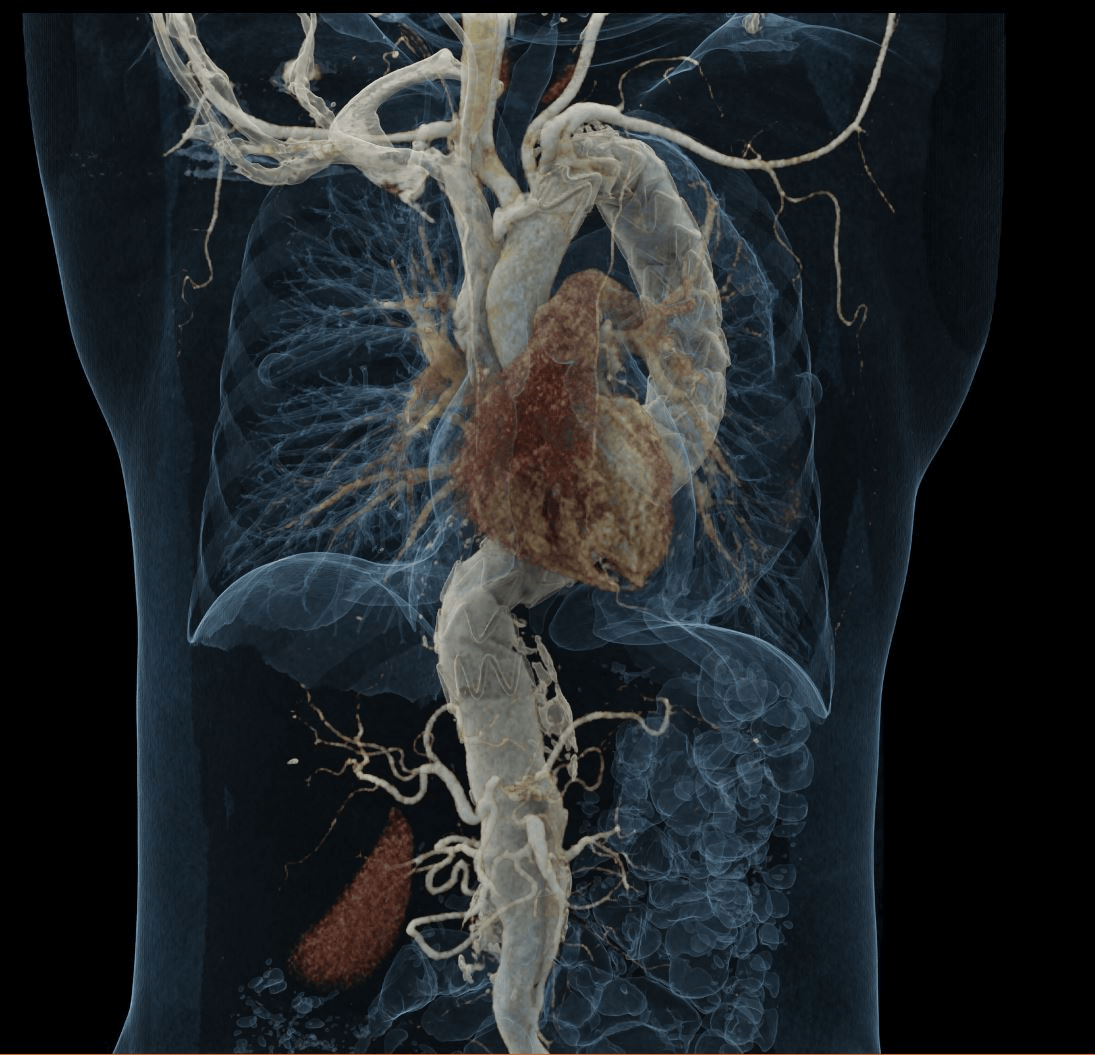

Chest X-ray showed mediastinal widening. CT angiography revealed a fusiform thoracoabdominal aortic aneurysm (89 × 85 mm, 221 mm length) from T6 to L2, with a dissection flap from the coeliac trunk to the infrarenal segment (Stanford B, DeBakey III), plus intramural thrombus and mural calcifications. A 10 mm flap in the proximal coeliac trunk and an intimal tear at the origin of the left subclavian artery (extending 54 mm) were also seen. Additional findings: left pleural effusion and hepatic haemangiomas.

Diagnosis: thoracoabdominal aneurysm with Stanford B, DeBakey IIB dissection. Medical management: IV nitroprusside, esmolol, and analgesia. Due to high rupture risk, endovascular repair was chosen over open surgery. Via right femoral access, two endografts were deployed in the thoracic/abdominal aorta. The left subclavian artery, arising from the false lumen, was not fenestrated. The procedure involved bleeding requiring transfusion, but no further complications.